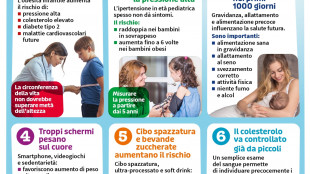

Cefalea digitale, sempre più studi collegano schermi e mal di testa nei ragazzi

Pediatri: "Provoca affaticamento visivo, sonno alterato e sovraccarico cognitivo"

Obesità, diabete e ipertensione, i rischi per il cuore iniziano da piccoli

Linee guida dai pediatri: "Monitorare pressione e colesterolo già nei primi anni di vita"